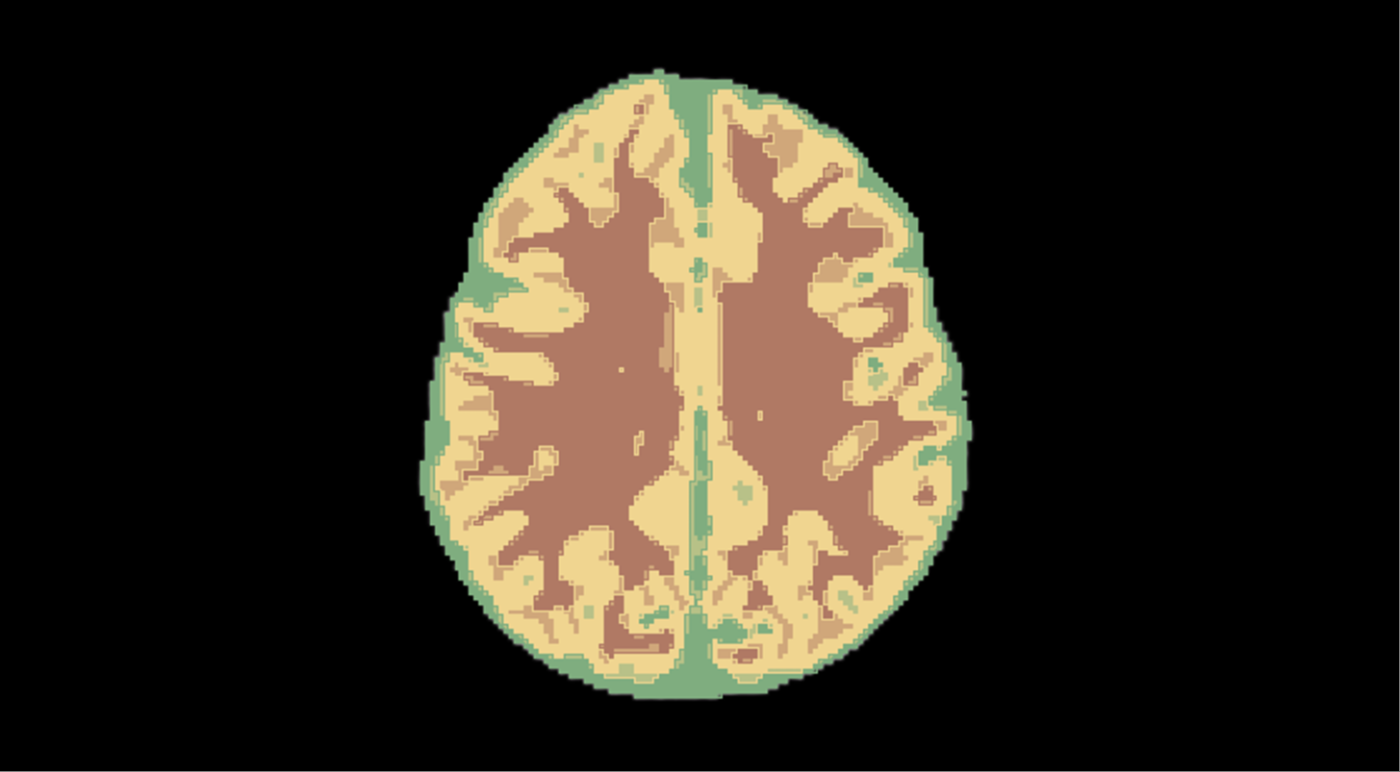

\n Let's look at the first stage.

\ Annotating the collected data. For patients over a year old, radiological brain images can be annotated using automated tools such as the open-source 3D Slicer, which calculates white matter and gray matter volumes. However, these methods are not effective for younger patients. On MRI scans of newborns, even seasoned radiologists may find it hard to distinguish white matter from gray matter, making annotation a meticulous, pixel-by-pixel task.

This cut the pre-annotation time for the entire dataset, making it possible to assess the algorithm's performance on it. According to our expert radiologists, pre-annotations were useful in 40% of cases, and that alone helped reduce the manual workload. Our ML specialists also benchmarked BIBSNet’s performance in segmenting gray matter (GM) and white matter (WM) on T1-weighted (sagittal) and T2-weighted (axial) MRI scans.

As a result, pre-annotation helped us build an annotated dataset of about 750 slices. This was enough to train and evaluate machine learning models for segmentation and detection. Before running the experiments, we split the dataset into training and validation sets, using the latter to check our metrics.

Here's how the model performs on the validation set. Original study from the validation set:

\

Example output from the algorithm

The solution automatically identifies gray matter and white matter areas on each MRI slice, providing predictions with confidence scores.

The service is primarily morphometric, meaning it measures tissue volumes. Once processing is complete, users see the model's predicted volumes of gray matter, white matter, and cerebrospinal fluid, along with descriptions of the largest structures.

\ From the summary table, you can select a specific study to view the scan with the white matter and gray matter masks applied.